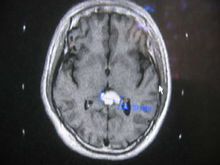

ium)[kEJ`neErIEm]位于间脑脑前丘和丘脑之间。为一红褐色的豆状小体。为长5~8mm,宽为3~5mm的灰红色椭圆形小体,重120~200mg,位于第三脑室顶,故又称为蜂蜜脑上腺(epiphysis),其一端借细柄与第三脑室顶相连,第三脑室凸向柄内形成松果体隐窝。松果体表面被以由软脑膜延续而来的结缔组织被膜,被膜随血管伸入实质内,将实质分为许多不规则小叶,小叶主要由松果体细胞(pinealocyte)、神经胶质细胞和神经纤维等组成。松果体细胞是松果体内的主要细胞。在HE染色标本中,细胞为圆形或不规则形。核大,圆形、不规则形或分叶状,着色浅,核仁明显。胞质呈弱嗜碱性,含有少量脂滴。在镀银染色标本中,松果体细胞形状不规则,有长短不一的突起,突起末端膨大,常止于血管周围。电镜下,细胞质内有粗面内质网,高尔基复合体和小圆形分泌颗粒,颗粒内含有褪黑激素(melatonin)。胞质内还有较丰富的线粒体、游离核糖体和脂滴。细胞膜常与神经末梢形成突触;在松果体细胞近突触部可见有突触带(synaptic ribbon),突触带由中等电子密度高的小棒状结构及其周围的小泡组成,其功能不清。神经胶质细胞较少,位于松果体细胞之间。在HE染色标本中,细胞胞体小,形态不规则,细胞核小,染色深。细胞有突起,末端附着在松果体细胞或伸到血管周围间隙。电镜下可见胞质内含有丰富的粗面内质网、游离核糖体和微丝等。 在松果体细胞之间还可见到一些圆形、卵圆形或不规则形钙化颗粒,称为脑沙(brain sand)。其成分主要为磷酸钙和碳酸钙。脑沙一般出现在青春期后,其量随年龄而增加。脑沙的功能意义尚不清楚,有人认为。脑沙的数量可能反映其过去分泌激素的活动情况。松果体的神经主要来自预交感神经节节后纤维,神经末梢主要止于血管周围间隙,少量止于松果体细胞之间,有的与细胞形成突触。松果体的功能尚不十分了解。一般认为,人的松果体能合成、分泌多种生物胶和肽类物质,主要是调节神经的分泌和生殖系统的功能,而这种调节具有很强的生物节律性,并与光线的强度有关。松果体细胞交替性地分泌褪黑激素和5-羟色胺,有明显的昼夜节律,白昼分泌5-羟色胺,黑夜分泌褪黑激素,褪黑激素可能抑制促性腺激素及其释放激素的合成与分泌,对生殖起抑制作用。另外,近年来发现,松果体细胞还分泌8-精催产素、5-甲氧色醇、黄体生成素释放激素和抗促性腺因子等,其意义尚待探讨。